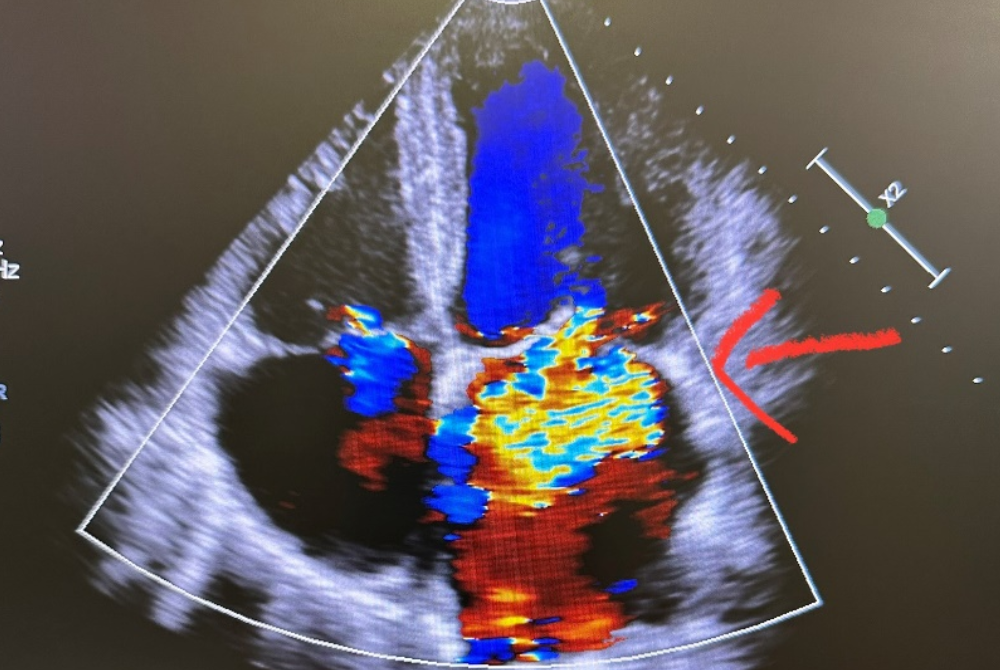

Dr Hashbullah also noted that the most common cause of sudden cardiac arrest in young athletes is hypertrophic cardiomyopathy (HCM), accounting for 36 per cent of deaths in one study.

"HCM is a disease characterised by hypertrophy of cardiac muscle (big heart muscle) without dilation of the left ventricle (bottom left of the heart muscle)," he explained.